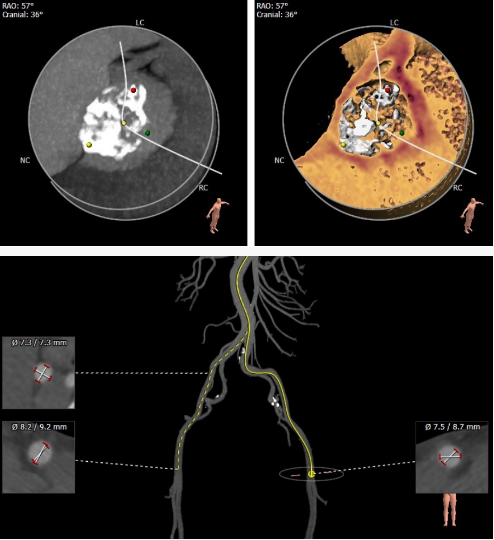

CT影像筛查

瓣环平面测量

找到窦底(二叶瓣 )

确定瓣环平面周长79.9mm

直径25.4mm

确认冠脉风险,左右冠高度尚可,冠脉平面

窦部大小

左室流出道:

Min: 22.7mm

Max: 32.9 mm

Average: 27.8 mm

心室大小

STJ

升主动脉

体位选择

选取合适的投射角度,三个窦底部在一个平面上,同时无冠窦在最低点

可以术中造影确认角度是否合适

钙化评估

股动脉入路情况

根据术前评估为type2二叶瓣,极重度钙化,左右窦左无窦有钙化粘连,窦部较小,术中需要囊扩张确认冠脉情况。考虑到瓣上结构瓣膜预选L29,直径满足要求,主动脉弓锐角,术中过弓谨慎。